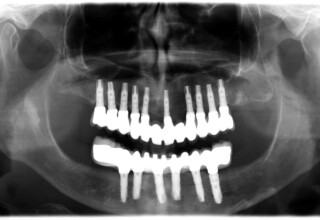

Full mouth prosthetic reconstruction on implants with a different approach on upper and lower jaw

Lower jaw: extractions, direct implant placement and immediate loading (same day) with a transitional bridge.

Upper jaw: Sequential extractions, sequential implant placement and gradual incorporation in the temporary bridge so that the patient was never left without fixed teeth. The aim of the above approach was to have the patient in continuous functional and aesthetic reconstruction, without immediate loading due to anatomical restrictions. Old smiling photos of the patient were used because the natural shape of the teeth was completely lost due to repetitive prosthetic attempts. Tooth relationship and teeth-lip support was transferred to the temporary restorations. Two different transitional bridges were needed to fully estimate phonetics, mastication and esthetics. After the necessary adjustments were finalized, the temporary bridge was used as a guide for the permanent bridges.